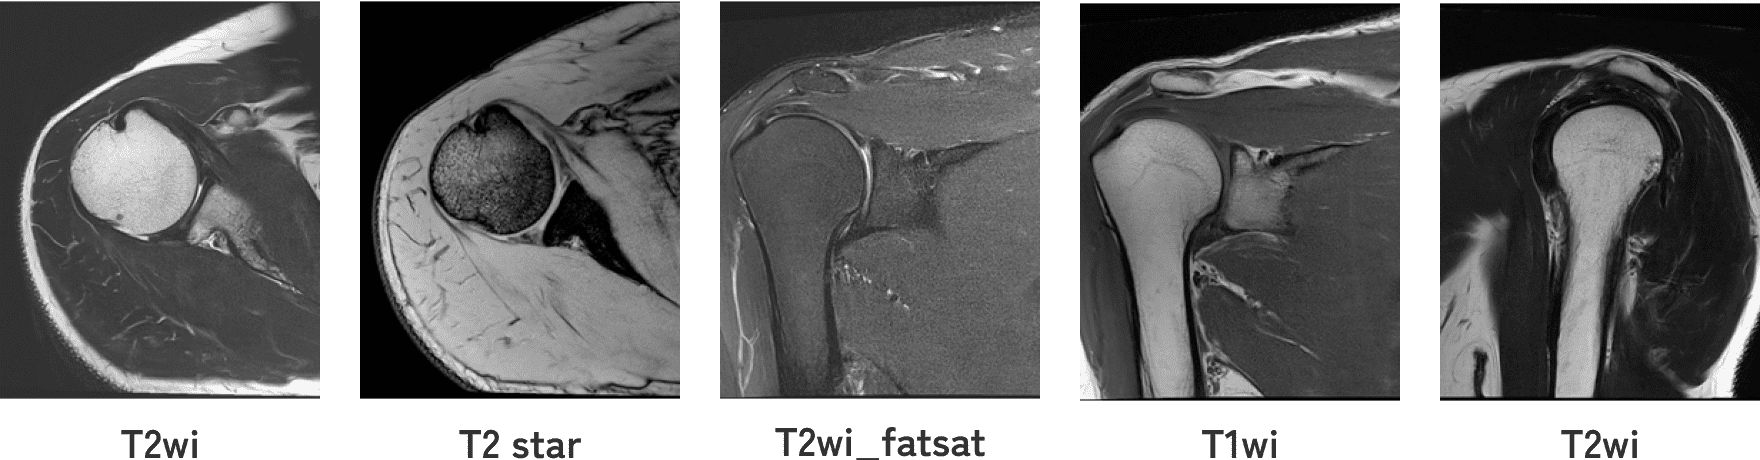

関節唇および肩甲上腕靱帯の正常変異とMRI画像所見のポイント。医療機関の方へ|御池クリニック。SLAP損傷 | ラドライフ。「関節のMRI」上谷 雅孝 / 青木 隆敏 / 神島 保定価: ¥ 13000#上谷雅孝 #上谷_雅孝 #青木隆敏 #青木_隆敏 #神島保 #神島_保 #本 #自然/医療・薬学・健康裁断済みのため全体的に状態が悪いとしております。口腔外科学 第4版 医歯薬出版 裁断済み。。医療機関の方へ|御池クリニック。素人裁断であることをご了承ください。また、本商品の他にも多数医学書を出品しておりますので、合わせてご検討ください。【koro】イラスト解剖学 改訂10版 最新版